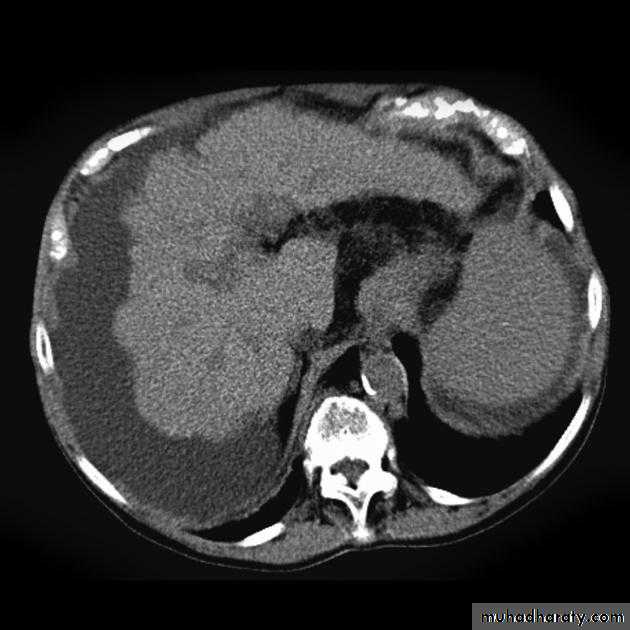

In portal hypertension, the pressure in the portal venous system is elevated due to obstruction of the blood flow in the portal or hepatic venous system. Cirrhosis is the commonest cause. Other causes include the occlusion of the hepatic veins (Budd-chiari syndrome) and thrombosis of the portal vein following infection of the umbilical vein in neonates or secondary to acute pancreatitisThe signs of liver cirrhosis at CT and US are :

1.reduction in size of the right lobe of the liver2.irregularity of the surface of the liver

3.splenomegaly

4.ascites

5.coarse abnormal liver texture at US while at CT, the parenchyma appears normal until late in the disease.

Patency of the splenic, portal & hepatic veins can be assessed with Doppler US,CT&MRI